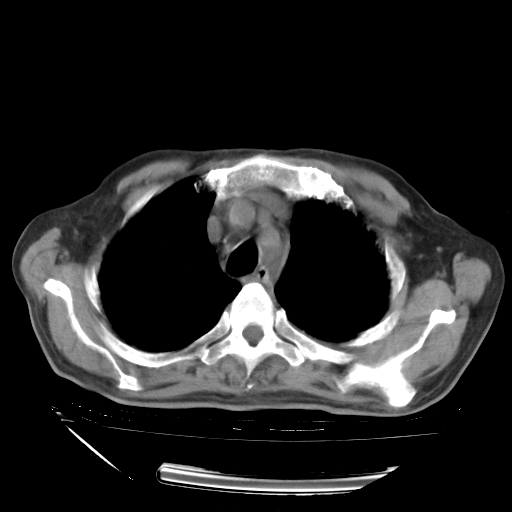

甲强龙80mg/日+抗结核治疗(异烟肼+利福霉素+乙胺丁醇)10天。复查肺部CT。

治疗10天肺部CT